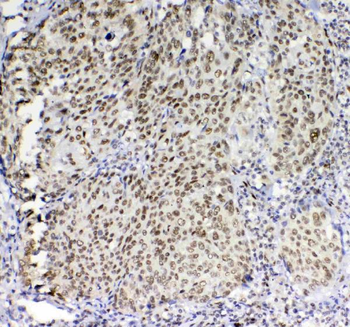

- Anti-GSTM3 Antibody [orb402287]

ELISA, IHC, WB

Human, Mouse, Rat

Rabbit

Polyclonal

Unconjugated

10 μg, 100 μg - Anti-S100 alpha 6/S100A6 Antibody [orb315184]